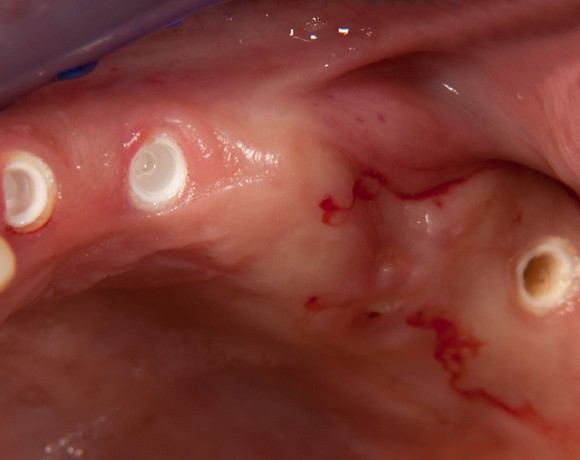

Bei dieser Patientin mussten die Zähne 22,26 und 27 aus parodontalen Gründen entfernt werden. Nach Extraktion der Zähne 22 und 26 wurden sofort in die Extraktionsalveolen die Implantate gesetzt. Zahn 27 war bereits sechs Monate zuvor extrahiert worden und die Knochenwunde gut ausgeheilt. Das geringe Knochenangebot wurde mit einem internen Sinuslift ausgeglichen. Im Bereich des Zahnes 23 wurde noch ein weiteres Implantat gesetzt. Da der Zahn 12 nicht angelegt und die Symetrie auf dieser Seite gestört war, wurden die Zähne 11 und 13 mit Teilkronen versorgt, um die Lücken zu schließen der Zahn 13 zu 12 umgebaut.